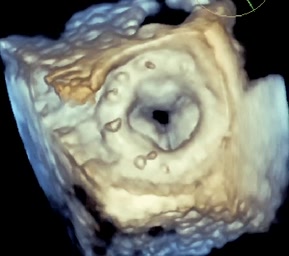

Bicuspida aortica senza stenosi valvolare

Mauro Pepi